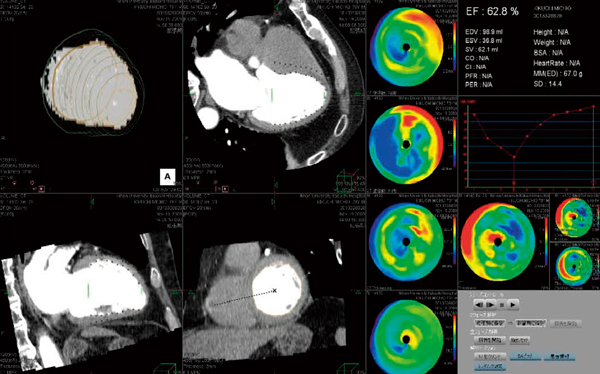

ManualによるCT心機能解析では,長軸像および短軸像ともに拡張期,収縮期を視覚的に判断し,設定することにより左室拡張末期容積(EDV),左室収縮末期容積(ESV),左室駆出率 (EF)を算出した(図3)。AutoによるCT心機能解析では,1心拍を10%ごとに10フェーズに分割し,これから得られるtime-volume curveからEDV,ESV,EFを自動算出した(図4)。ザイオソフト社製のソフトウェアでは,10フェーズの画像を取り込み,全フェーズ解析のボタンをワンクリックするだけで,十数秒程度で容易に心機能指標の自動算出が可能であった(図5)。自動解析にて得られる心機能指標はEDV,ESV,EFの ほか,身長,体重の入力によりCO,CI,PFR,PERなどのパラメータも算出可能であった。(図6)。

図6 心機能自動解析から得られるパラメータ